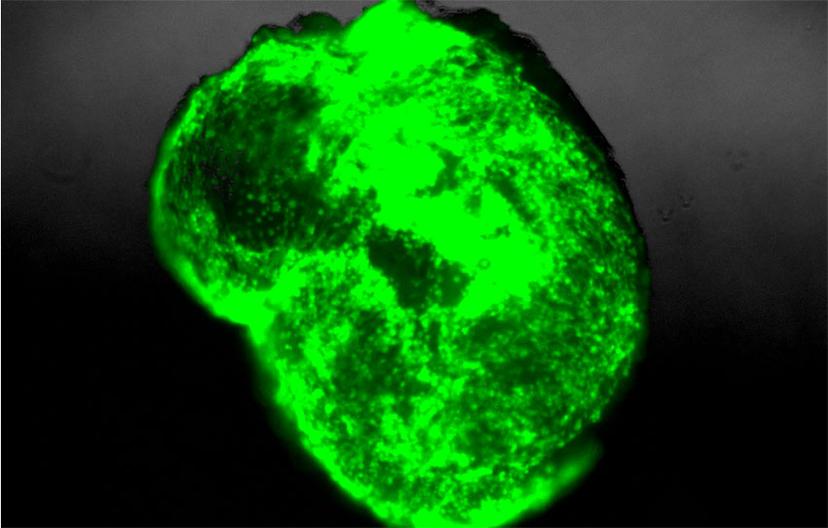

SS: Tell us about your glioma cerebral organoid model

AL: To address the limitations of current preclinical GBM models, we have retro-engineered patient-specific GBMs using patient-derived glioma stem cells and human embryonic stem cell (hESC)-derived cerebral organoids. Our cerebral organoid glioma (GLICO) model demonstrates a clear infiltration of the human cerebral organoid by the patient-derived GSCs. Following the invasion into the organoid, the GSCs then proliferate and migrate throughout the host tissue, ultimately forming tumors that closely phenocopy patient glioblastomas.

AL: Our GLICO model addresses a number of the limitations of current preclinical GBM models, as it allows us to study patient-specific GBMs within a human microenvironment similar to that of a normal human brain. Additionally, our cerebral organoids cultured and differentiated in Corning Matrigel matrix, allows us to recapitulate the same biological behavior and histopathological features of patient GBMs. Our findings also show that GLICO tumors are supported by a network of interconnecting microtubes that facilitate the invasion and proliferation of the glioma stem cells within the organoid.